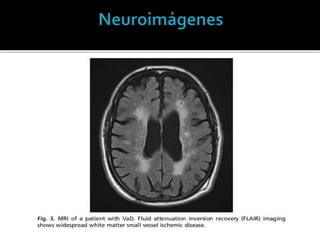

 Resonancia más sensible que laTomografía.

 TAC: Información suficiente.

 Infartos corticales y subcorticales.

 Leukoaraiosis

Los criterios radiológicos solos no

permiten diferenciar pacientes con o

sin demencia vascular.

 Leukoaraiosis: Lesiones en sustancia blanca.

 No son un hallazgo específico.

 Demencia // No Demencia.

 Infecciones, desmielinización, neoplasias,

desordenes metabólicos.

A. Lesiones extensas en

sustancia blanca.

B. Infarto cortical

C. Microsangrado

D. Múltiples infartos lacunares.